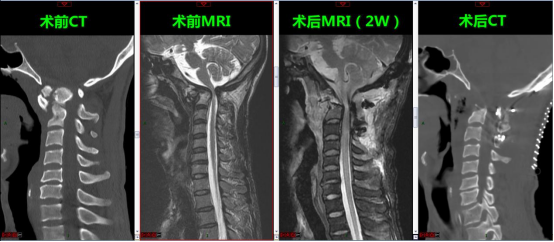

术前术后影像对比

术前、术后影像对比–上颈段脊髓长期受压萎缩,减压术后脊髓变性扩张不全